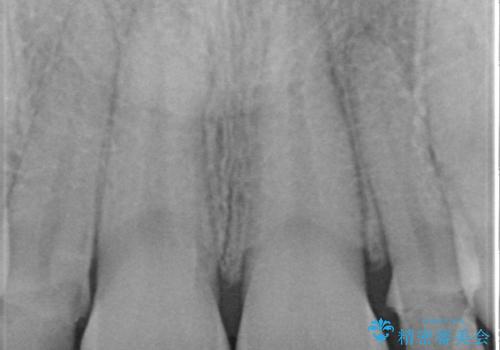

左右の前から2番目の歯が細く、矮小でした。

内側に入っている左上5を抜歯しています。

抜歯したスペースを使い、歯並びを整え、さらにその隙間を利用して細い歯を大きく整えてセラミックで被せるという総合的な治療を行いました。

マウスピース矯正→上顎両側2番のセラミック、左下67の虫歯治療 の順で行いました。